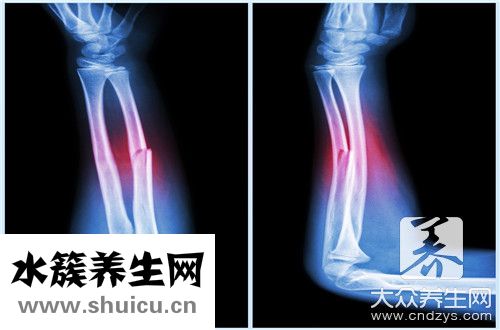

第五跖骨基底端因為是腓骨短肌和第三腓骨肌的支撐點經常非常容易產生疲勞性骨折或是撕脫性骨折。第五跖骨基底端骨折,務必確保充足的痊愈,假如痊愈不太好,通常會留有并發癥,例如慢性疼痛等。

因而,第五跖骨基底端骨折,不可以太早負重,假如太早負重會造成下列的問題:

第一,影響到骨折愈合,第二個可能造成骨折移位,過早的負重,不利骨折的痊愈。此外可能因為第三腓骨肌和腓骨短肌的伸展造成骨折再度移位,造成骨折畸型痊愈。骨折畸型痊愈后,部分因為之后活動受第三腓骨肌和腓骨短肌的伸展,非常容易造成部分的慢性疼痛,

因而,當產生第五跖骨基底端骨折時,建議立即到醫院門診就醫,依據醫師的具體指導下開展相對的康復訓練,防止太早負重。